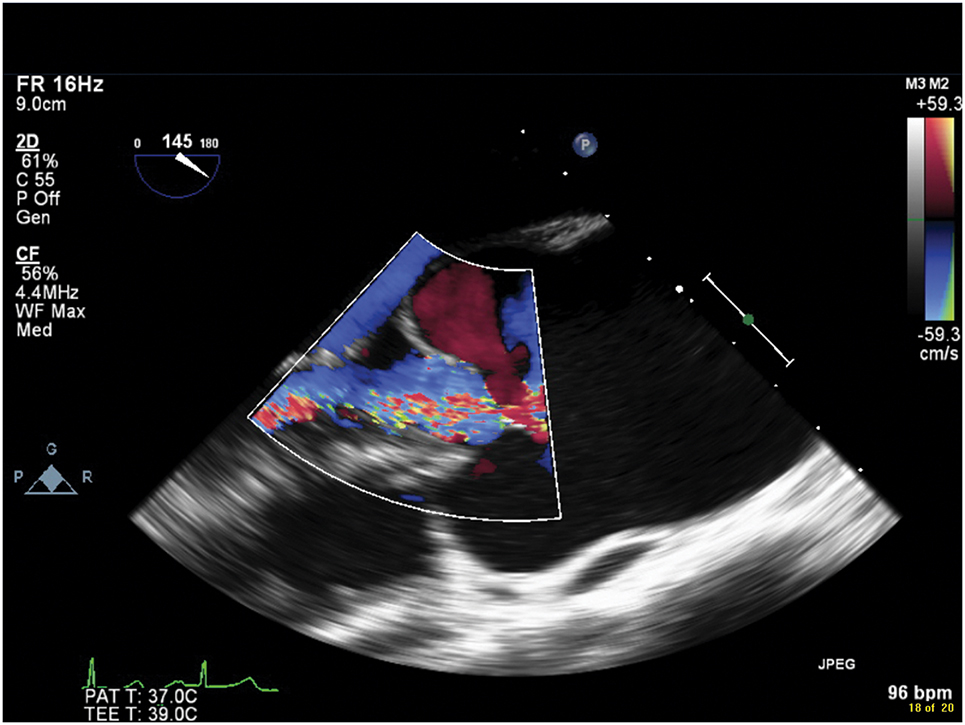

Figure 9.1.: Midesophageal Aortic Valve Long-Axis View on Transesophageal Echocardiography Demonstrating Moderate Central Aortic Insufficiency Secondary to Aortic Root and Ascending Aortic Dilatation in a Young Female with Turner Syndrome.

Midesophageal aortic valve long-axis view on transesophageal echocardiography demonstrating moderate central aortic insufficiency secondary to aortic root and ascending aortic dilatation in a young female with Turner syndrome.